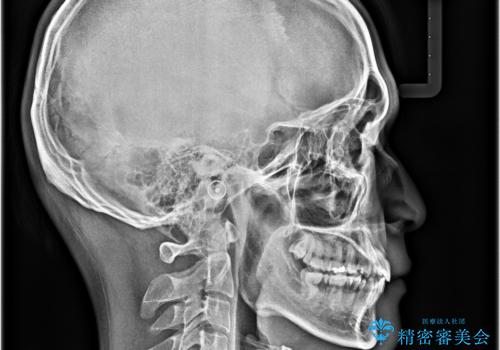

- 口元の突出感と奥歯の咬み合わせの悪さを気にして来院された患者様です。

口元はやや突出感があったため、上下左右の第一小臼歯4本を抜歯してワイヤー矯正にて抜歯矯正を行うこととしました。

また、左右ともに最後臼歯が交叉咬合になっており、外側に飛び出している上顎の最後臼歯を補助装置を利用して、積極的に内側に引き込むようにしました。

2年半の治療期間を想定しており、予定通りの期間で無事に終了することができました。

唇や顎先に力を入れないなくてもスムーズに唇を閉じることができるようになりました。